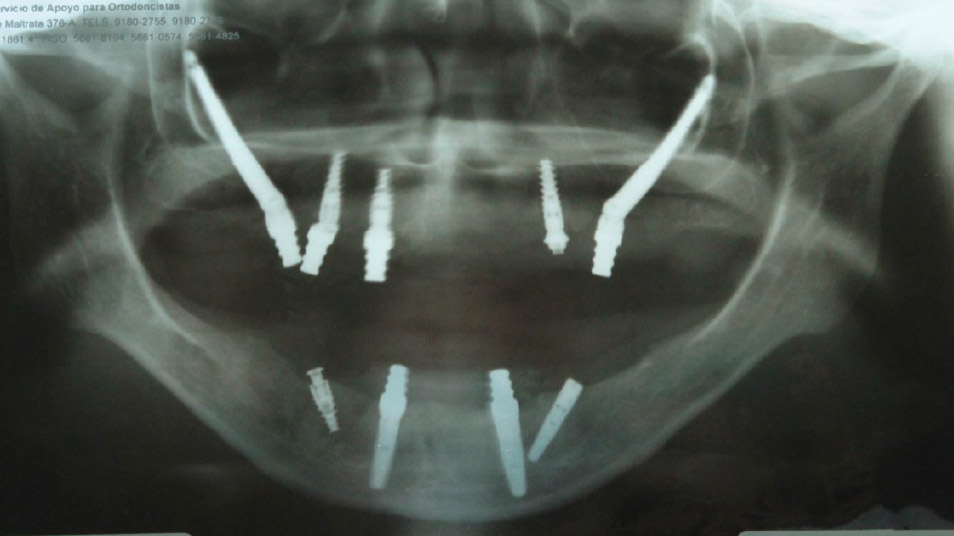

Behind every restored smile, there is precise planning. These radiographic studies show how advanced imaging and implant techniques allow us to transform even the most complex cases into stable, long-term solutions.

Our innovative techniques, including zygomatic and pterygoid implants, anchor directly into your natural bone structure, creating a strong and lasting foundation for fixed, beautiful teeth — even in the most complex cases.

Zygomatic Implants

Pterygoid Implants

Transnasal Implants